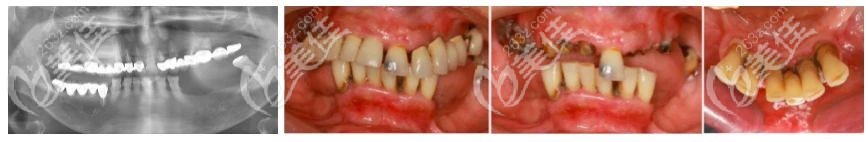

術(shù)前無牙頜老人口腔情況

口內(nèi)有多個不良修復(fù)體且余留牙均有松動,下頜后牙區(qū)的垂直向骨量吸收嚴(yán)峻,牙齒不整齊。